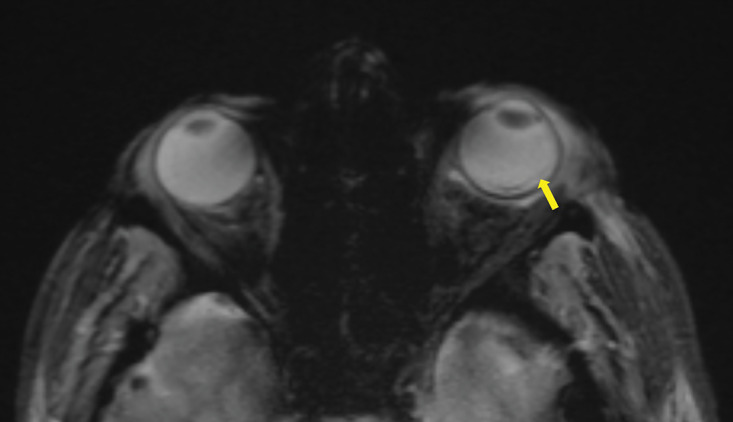

MRI Findings of Endogenous Endophthalmitis as a Complication of Pneumococcal Meningitis.

Teaching point: Endophthalmitis is an uncommon but severe complication of meningitis that can be visualized on MRI.